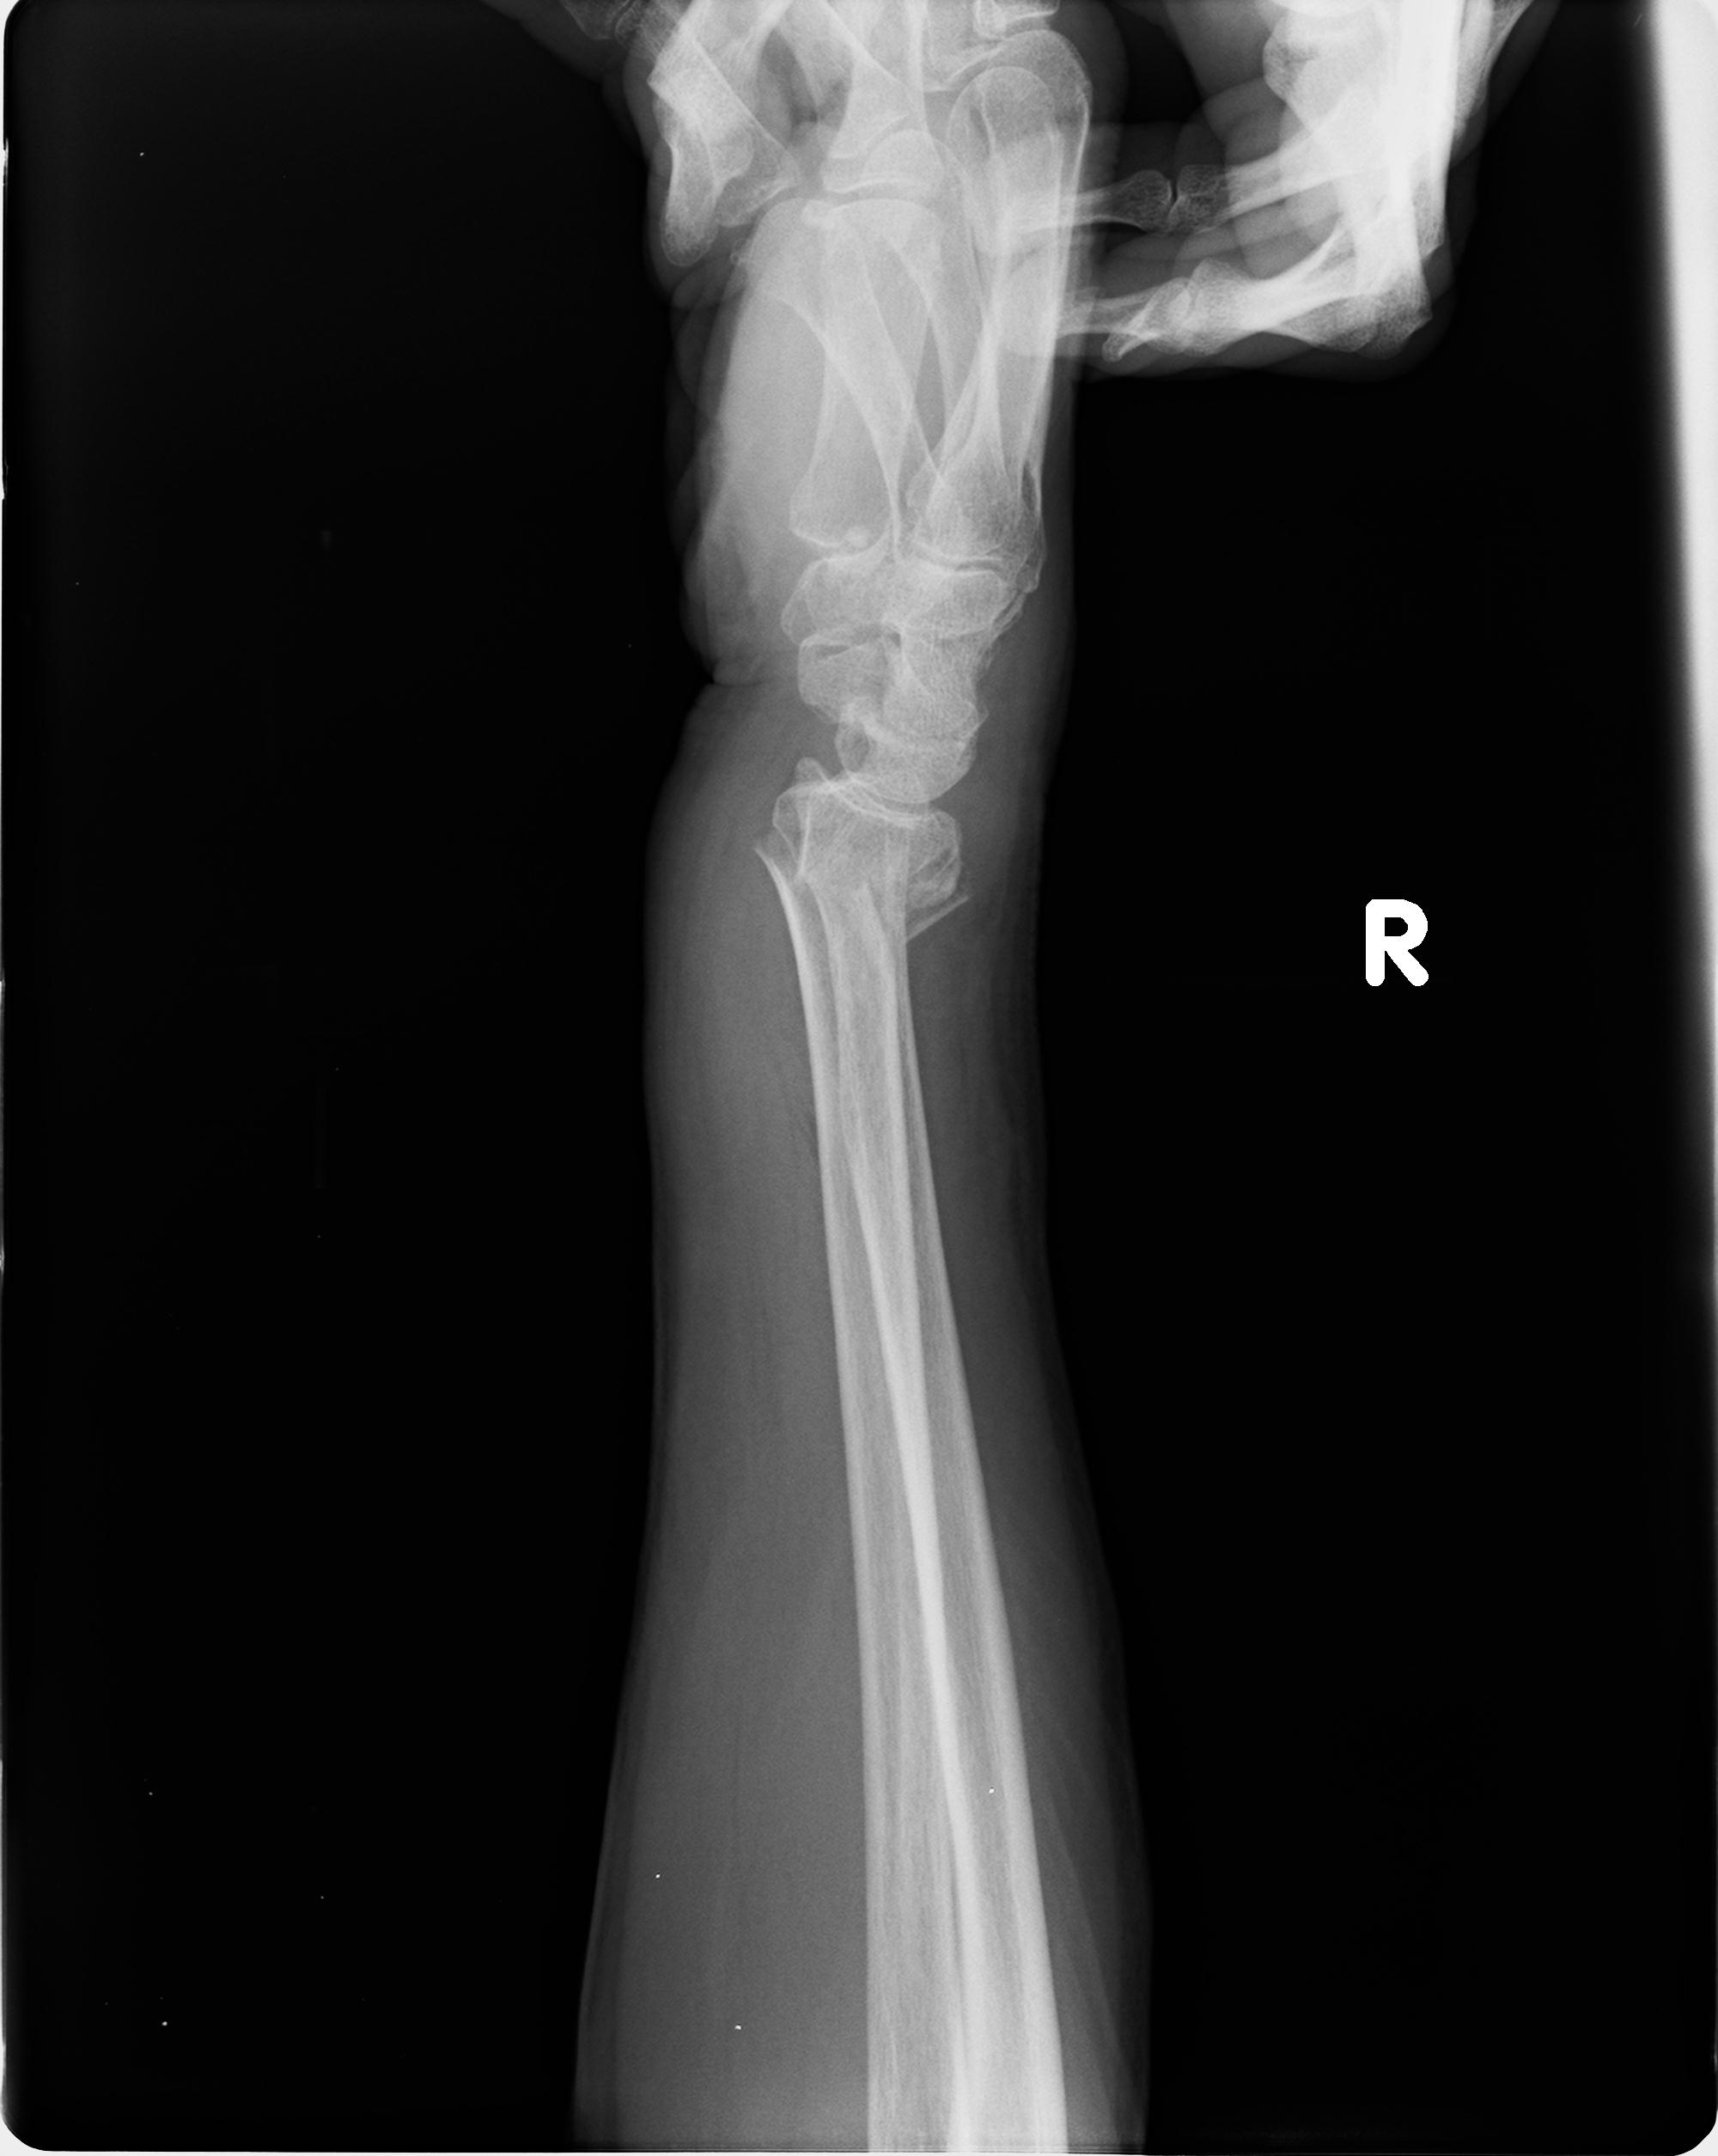

110211 1/6 1/8 左前腕 4R 15歳男性 橈骨骨幹部骨折